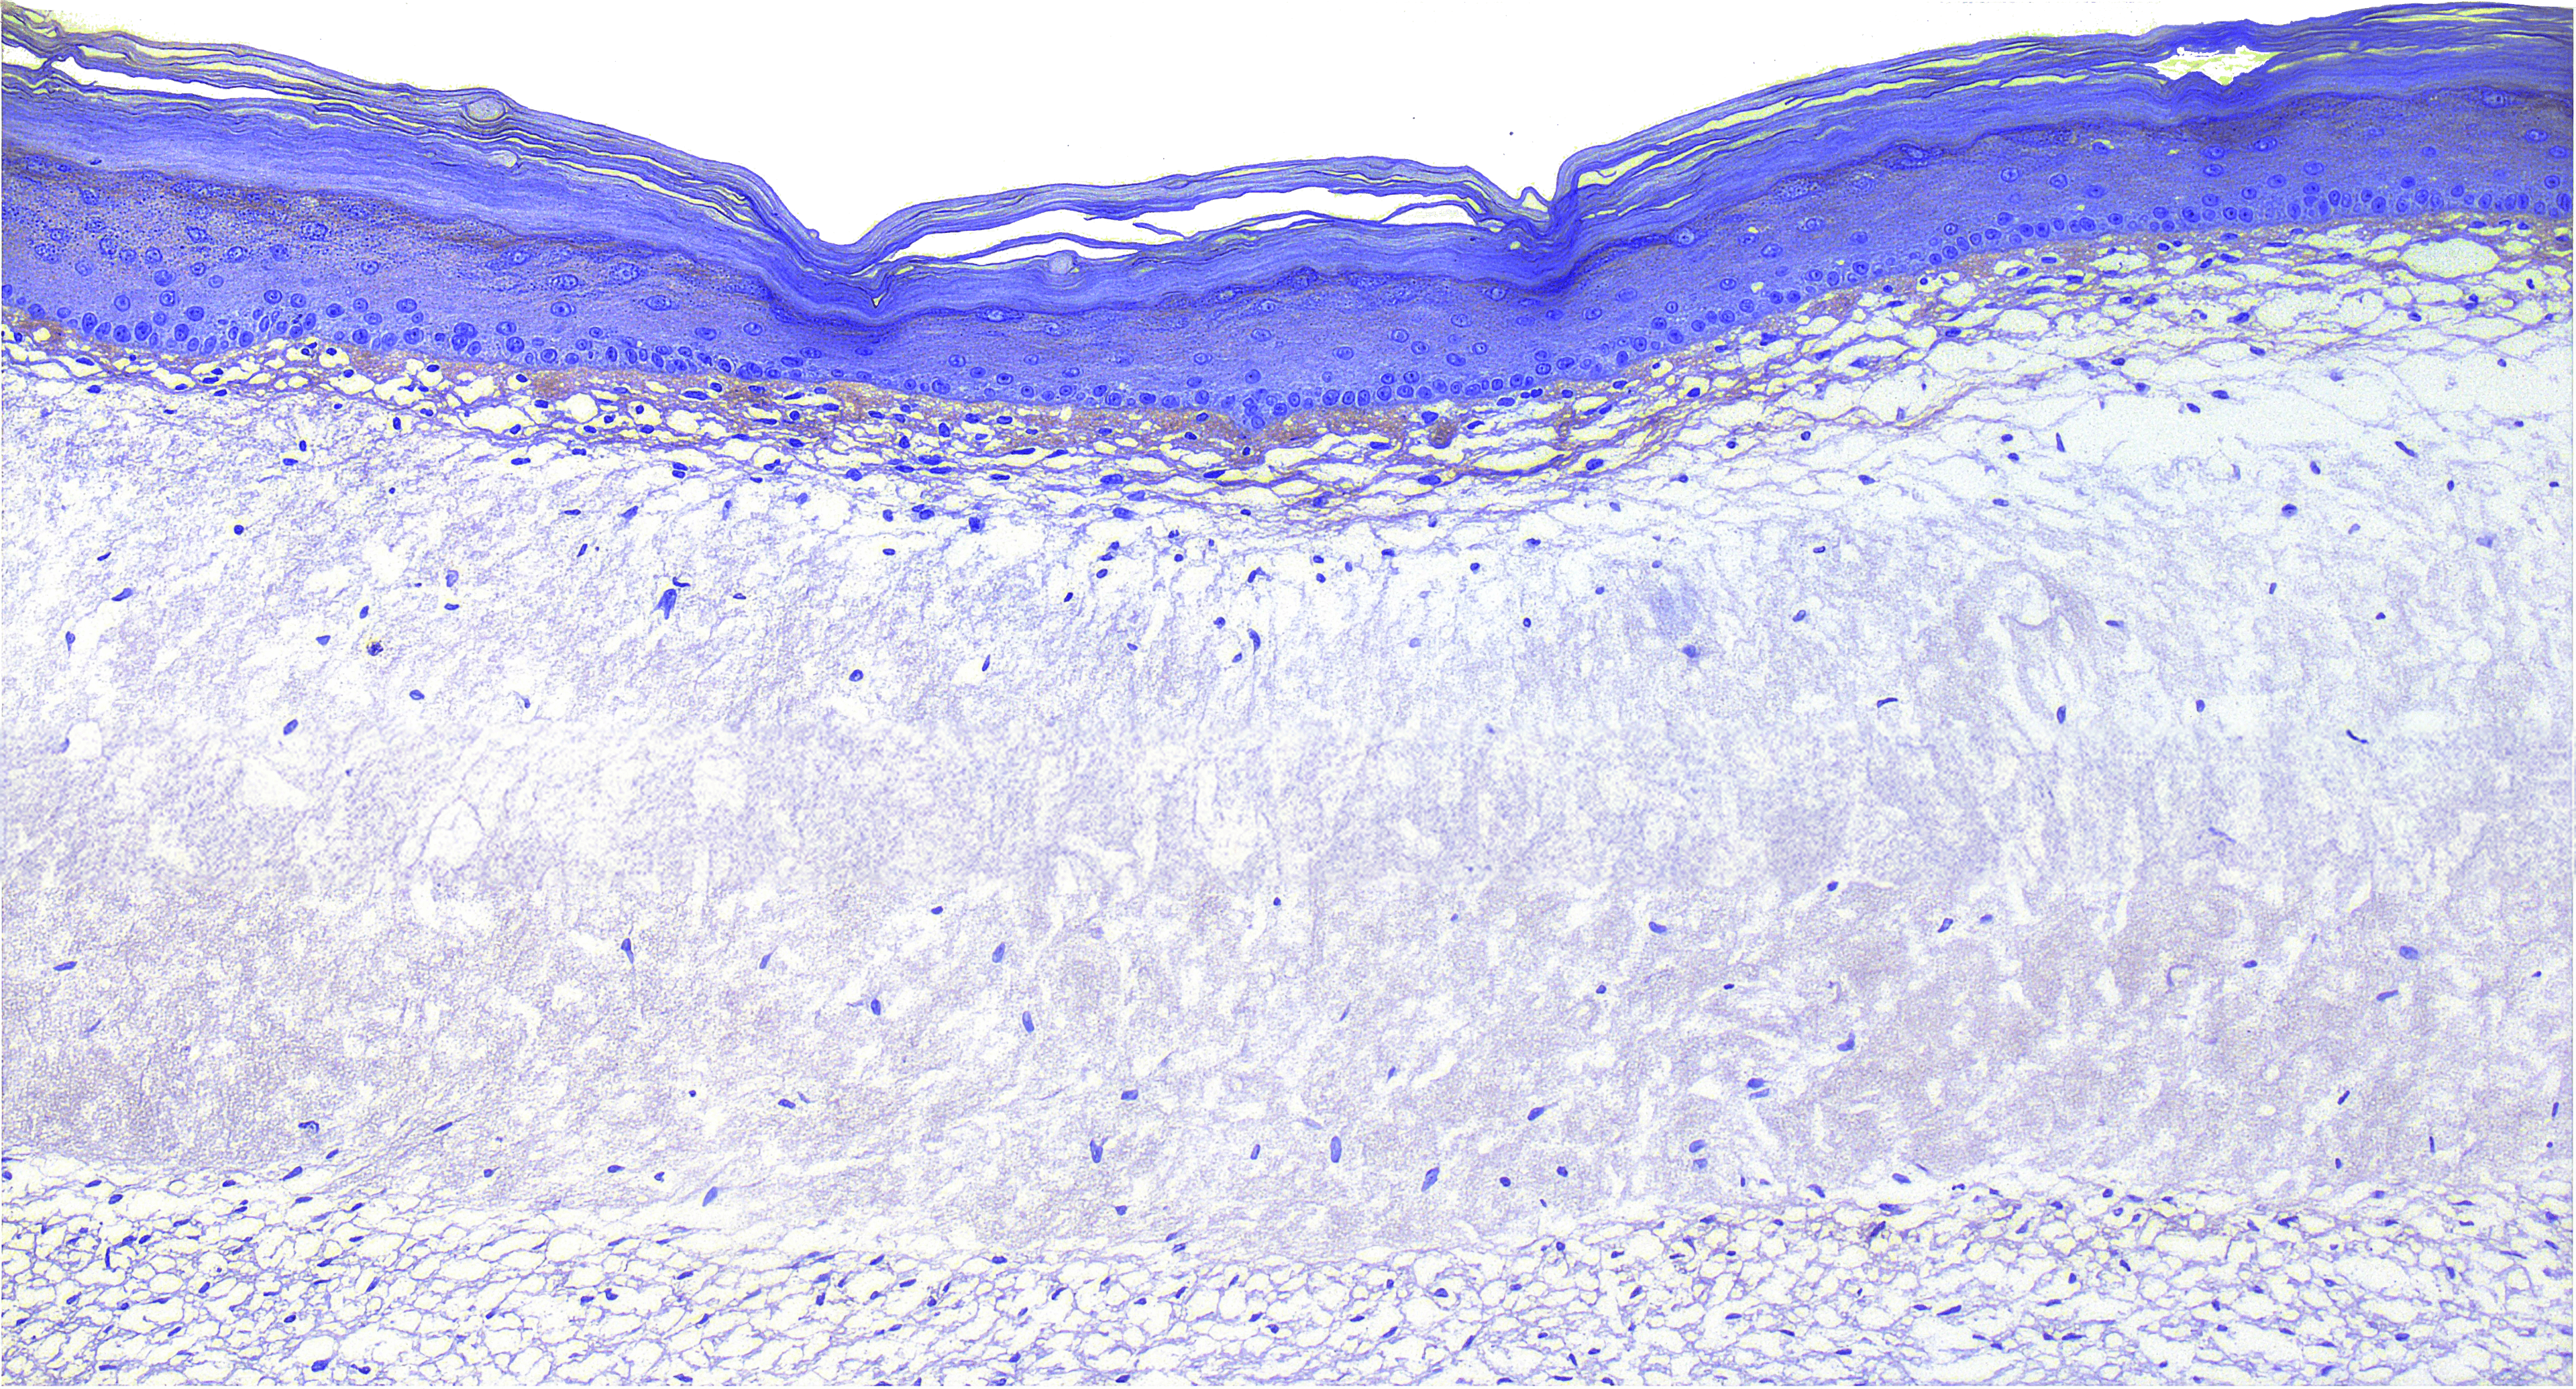

VitroScreen, a SenzaGen Group company, pioneers next-generation in vitro testing solutions. We leverage cutting-edge biological models—from 2D cells and reconstructed tissues to ex vivo systems and cellular spheroids—to deliver precise, human-relevant data for the Cosmetics, Medical devices, Nutraceuticals, Pharma and Chemicals industries.

Our models mirror human biology for precise, predictive accuracy.

We design and execute rigorous preclinical in vitro studies, combining validated testing standards with fully customized protocols to deliver reproducible, decision-ready results. Our expertise covers multiple product categories and therapeutic areas, providing highly predictive platforms for both regulatory and efficacy assessment.

Use of a 3D Model with Reconstructed Human Epidermis Infected with Fungi and Covered with a Bovine Nail to Simulate Onychomycosis and to Evaluate the Effects of Antifungal Agents

Hard Water on RHE - Dermatology Research

Anti-Inflammaging Cosmetic Action on RHE - CUDP-100003